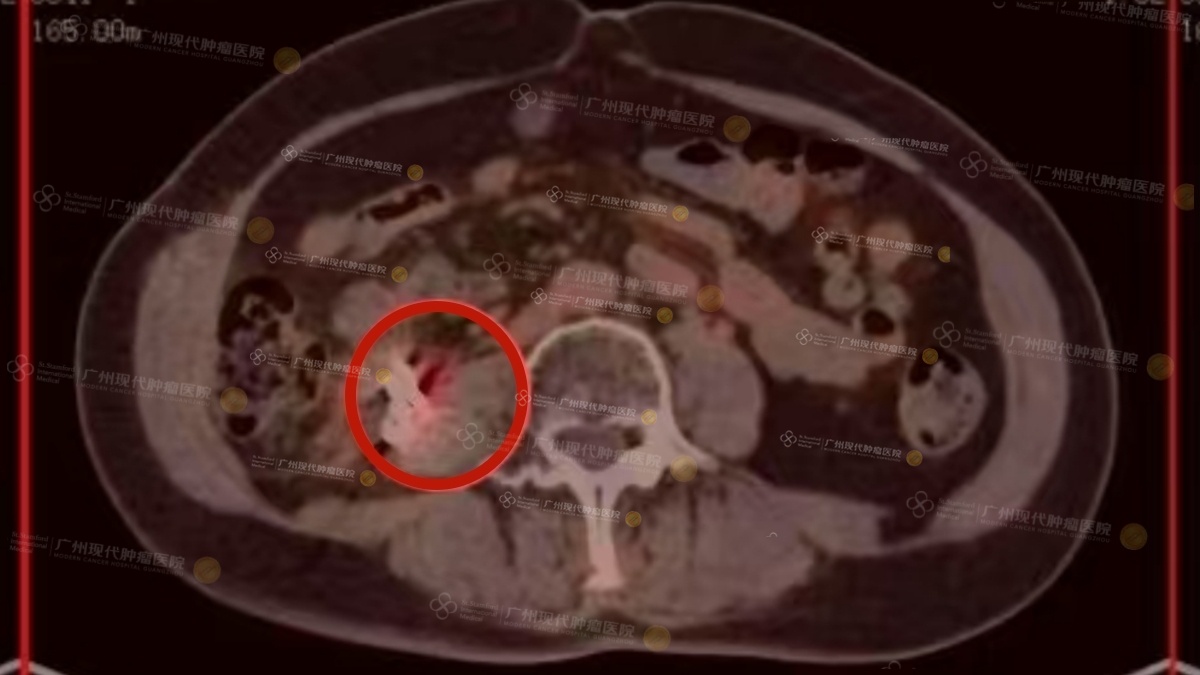

Kết quả kiểm tra mới nhất khiến tất cả đều thở phào nhẹ nhõm: chỉ số hoạt tính khối u đã giảm từ 5,9 xuống còn 3. “Phần lớn tế bào ung thư đã bị tiêu diệt, mức độ hoạt động giảm đi rất nhiều,” bác sĩ vui mừng chia sẻ.

Hình ảnh CT sau điều trị: Chuyển hóa của khối u giảm rõ rệt, SUVmax = 3,4.